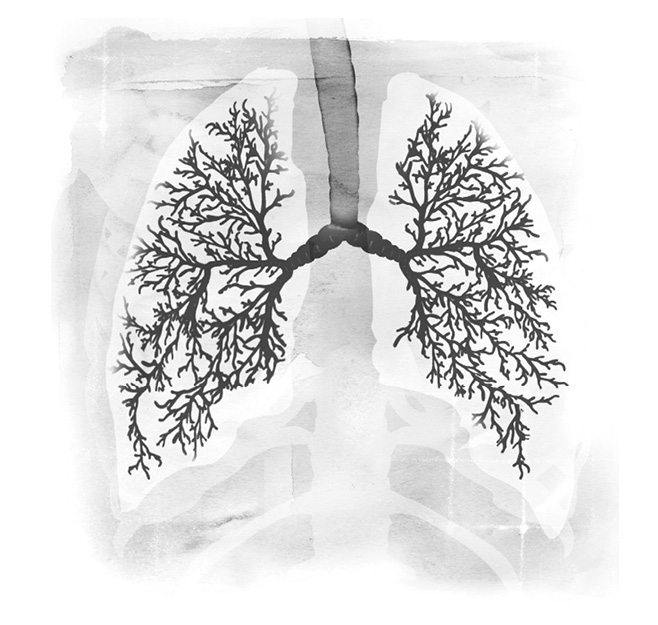

许多人对于肺脏的大小和位置缺乏正确的感知,他们所想的跟事实差距相当远。成人的肺脏大小变化很大,视性别、身高和姿势而定。

多数人身上的肺脏长度介于二十五至三十五公分之间,最宽的地方大约有十至十五公分。肺脏的形状像是切掉顶部的椭圆形,类似橄榄球的形状,不过比橄榄球小一些、窄一些,重量一般是○.九至一.四公斤重。

在左页的X光片中,你可以看到两侧肺脏的实际大小和位置。你所画的图跟这张X光片比起来,有没有什么不同呢?

肺脏的顶部延伸到锁骨上方,当你吸气吸到饱的时候,肺脏的底部几乎会延伸到肋骨的下缘。